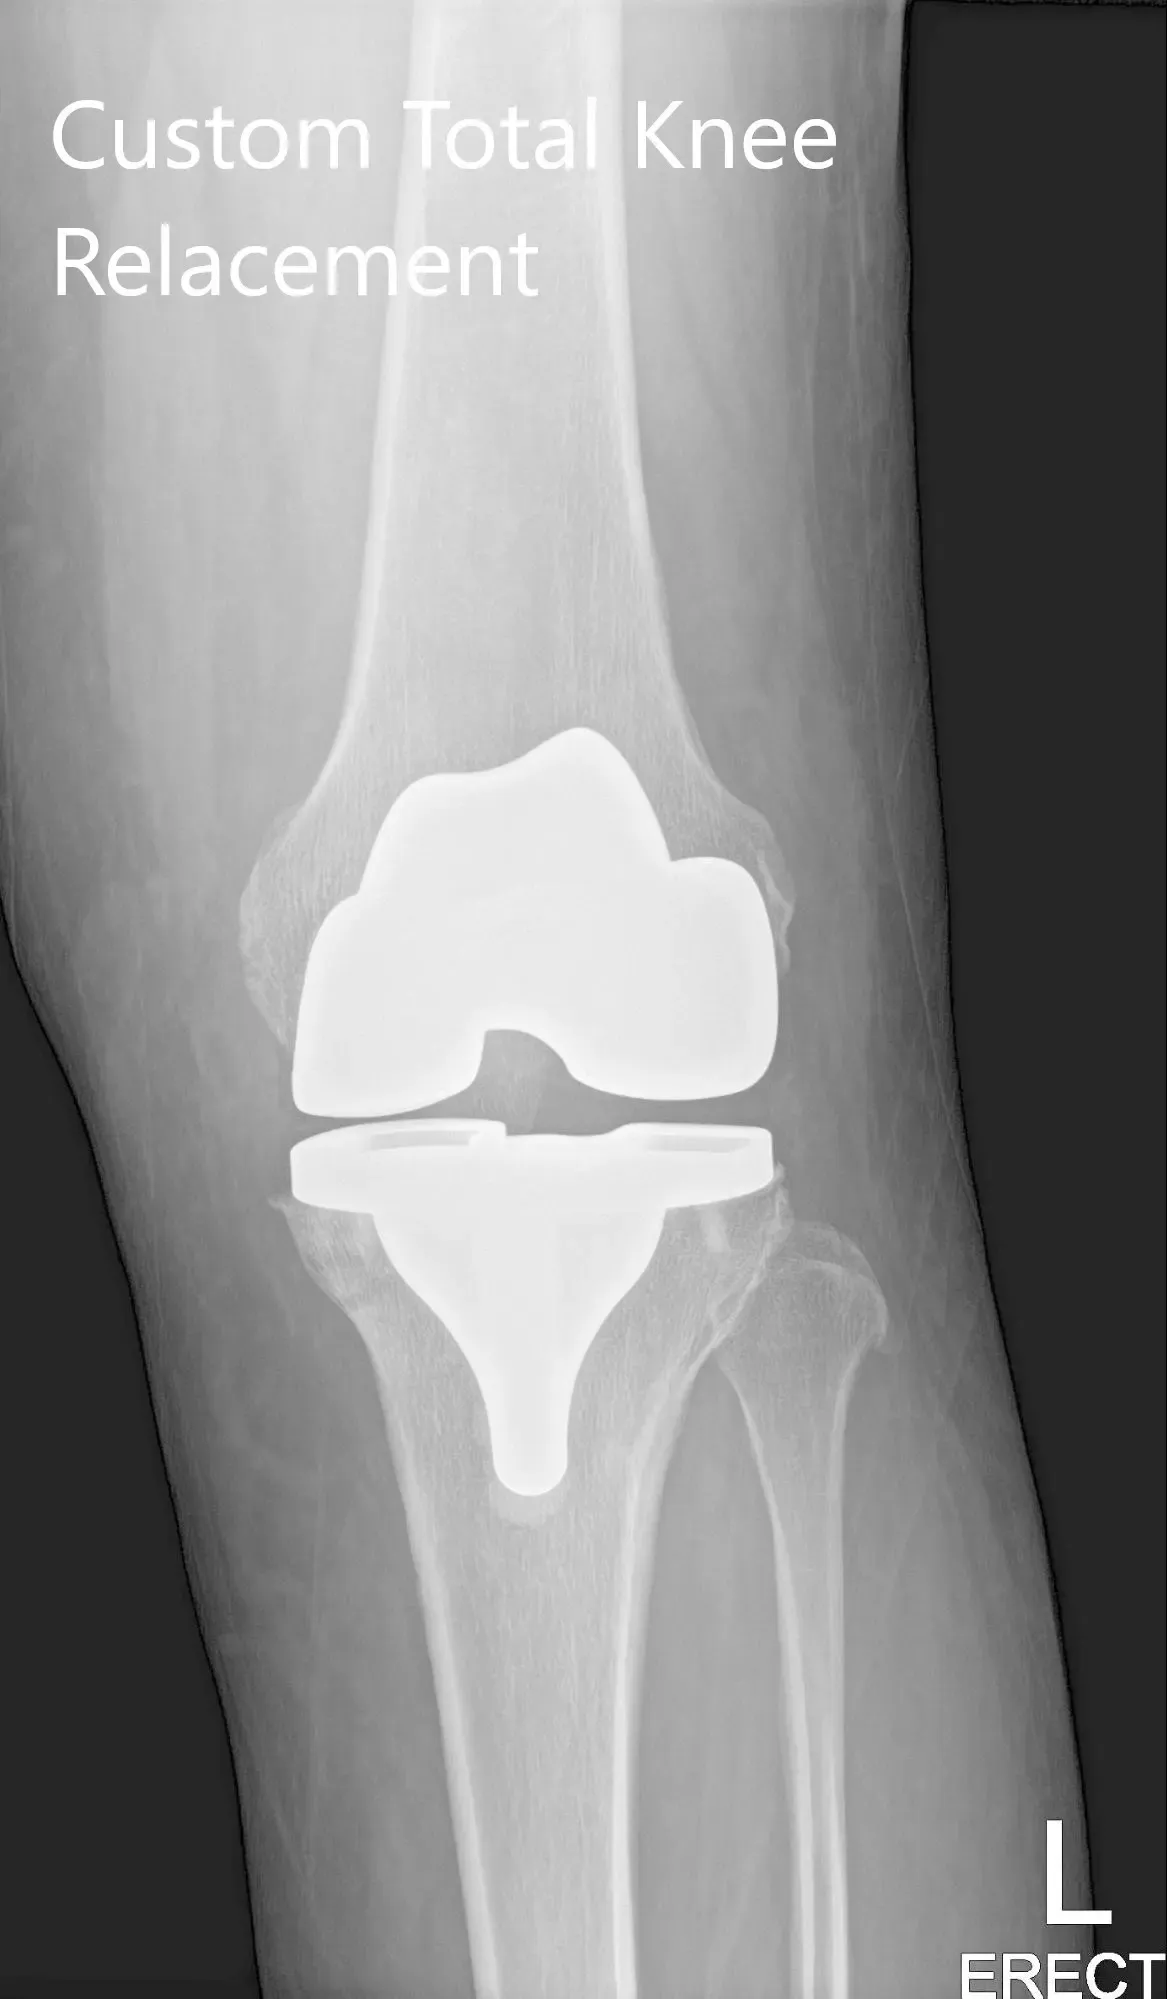

Imágenes de radiografías postoperatorias que muestran la visión AP y lateral de la rodilla izquierda.